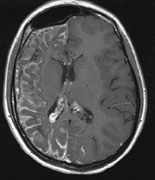

1. Schwannomas most commonly affect the fifth cranial nerve (CN), but any cranial nerve may be affected. In contrast to vestibular schwannomas (CN VIII), these typically do not grow large.84,90 Vestibular schwannomas (acoustic neuromas) are the classic finding in NF2 (Fig. 7). The risk for malignant transformation is low, but may be higher with radiation exposure.84,94

Fig. 7. Neurofibromatosis type 2: Images of a 12-year-old boy with deafness and weakness in his arms and legs, whose father has bilateral deafness. Axial T2-weighted (a) and postcontrast axial (b) T2-weighted images reveal bilateral vestibular schwannomas, which are also known as acoustic neuromas (arrows). This is the classic finding of NF2. (b, c) Bilateral schwannomas are seen in Meckel's cave (arrowheads) and a (d) lower left cranial nerve schwannoma extends into the pars nervosa of the jugular foramen (arrow). (e) A part cystic and part solid enhancing ependymoma in seen within the cervical cord and medulla and within the distal cord and conus. (e, f) Thoracic schwannomas are present at numerous levels (arrowheads). Marked enhancement and thickening of the roots within the cauda equina also represent multiple schwannomas.